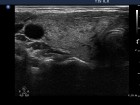

Follow-up examinations (rows from 1st to 8th):

Comments:

2. Note the relation between volume, echogenicity, vascularization and hormone levels.